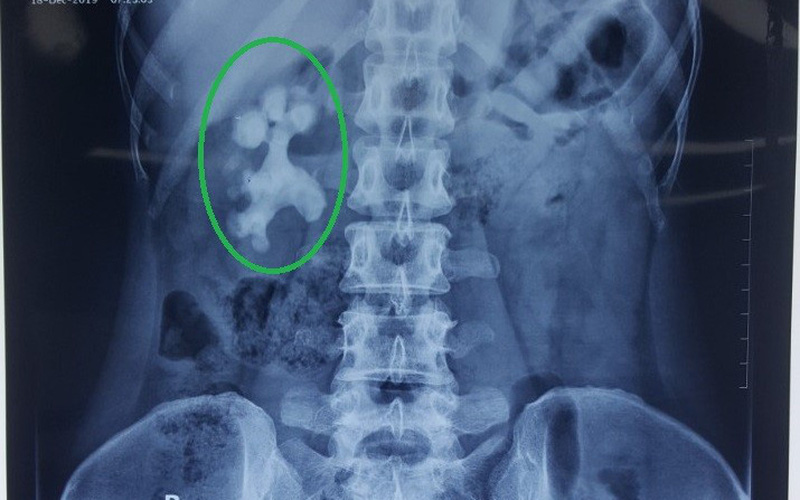

Sau khi được BSCKI. Nguyễn Đức Hùng, Phòng khám Thận niệu – Nam khoa kiểm tra và tư vấn thực hiện các xét nghiệm cận lâm sàng, kết quả cho thấy bệnh nhân có sỏi san hô phức tạp, lấp đầy các xoang thận với kích thước 6 – 7cm.

Tiến hành tán sỏi cho bệnh nhân. Ảnh: BVCC